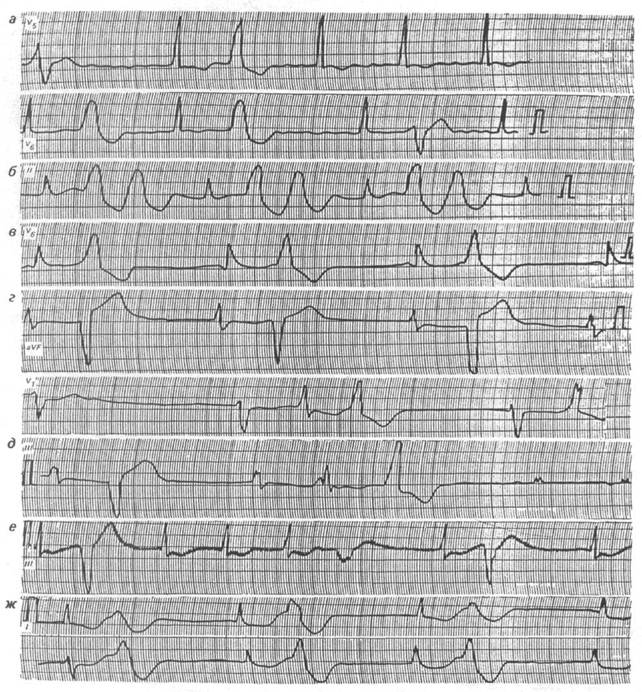

1) Оцените представленную ЭКГ.

1) На представленной ЭКГ желудочковая экстрасистолия, об этом свидетельствуют измененный комплекс QRS, интервал ТР, изменение в продолжительности цикла RR.